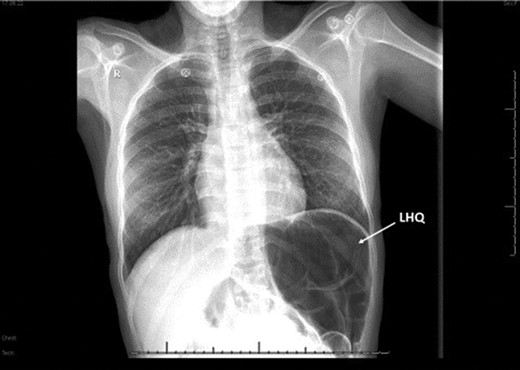

Laboratory investigation showed a white blood cell count of 15.13 × 103/UL, (mainly neutrophilia of 90.3%), a hemoglobin level of 9.4 g/dL, and a platelet count of 189 × 103/UL. The other biochemical parameters including liver enzymes were normal apart from a trace of jaundice, with total Bilirubin of 2.43 mg/dL and direct Bilirubin of 0.45 mg/dL. Chest X-ray showed bowel loops at the splenic fossa (Fig. 1). An initial diagnosis of a torted ovarian cyst was made. A pelvi-abdominal ultrasound revealed normal adnexa but a right-sided soft pelvic-abdominal mass with the absence of a splenic shadow at the left hypochondrium. Subsequently, CT scan of the abdomen and pelvis revealed a large right-sided infarcted spleen of 30 × 16 × 10 cm3 (Fig. 2) and a ‘whirl sign’ of the splenic pedicle (Fig. 3). Furthermore, CT scan showed signs of portal hypertension (Fig. 4) associated with mesenteric varices (Fig. 5). The patient subsequently underwent a surgical exploration.

Chest x-rays; absence of gastric bubbles at the left hypochondria (LHQ; white arrow) that was replaced with bowel loops.